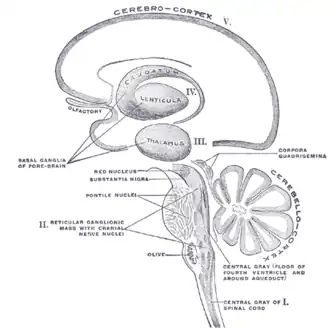

Schematic representation of the chief ganglionic categories (I to V)

Schematic representation of the chief ganglionic categories (I to V) -